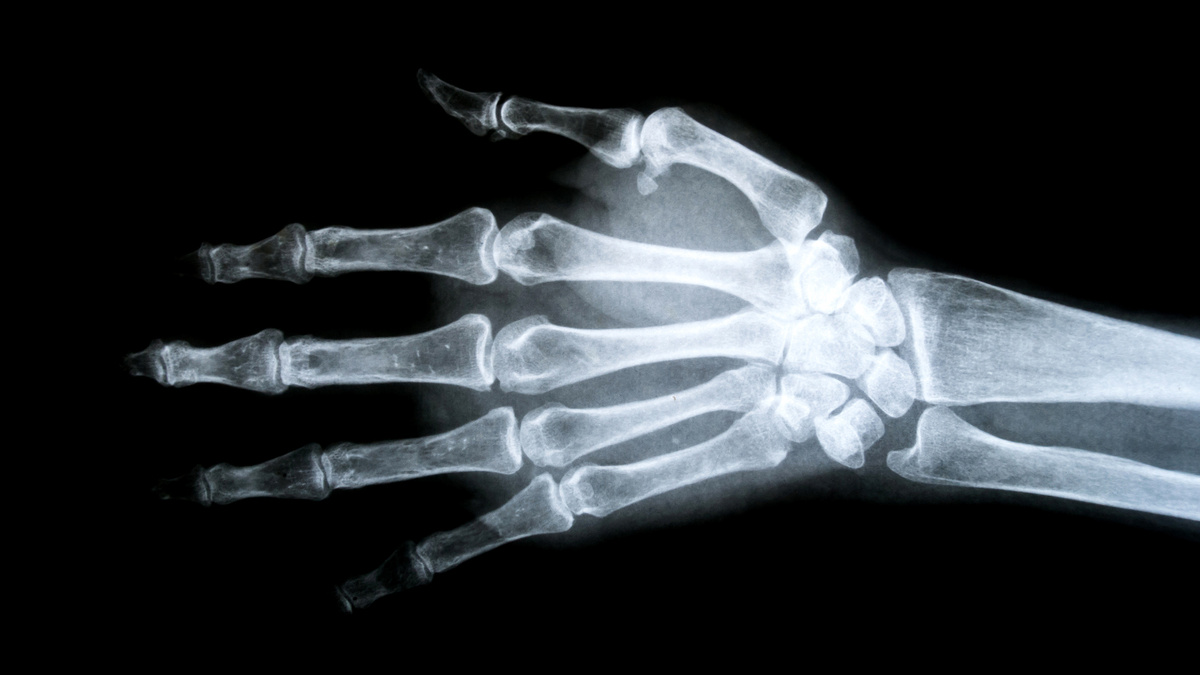

Фото: Thammanoon Khamchalee/Shutterstock/FOTODOM У людей с редкой мутацией в гене LRP5 кости во много раз плотнее нормы

Обычная человеческая кость ломается при нагрузке около 4000 ньютонов. Это как если бы на вас встал взрослый бегемот. Но не целиком, а только одной ногой. Правда, есть важное уточнение: человеческие кости не ломаются от статического веса. В реальности перелом происходит от резкого удара или нагрузки, когда вся эта энергия выделяется за доли секунды.

У людей с редкой мутацией в гене LRP5 показатель в разы выше. Например, после серьезной автомобильной аварии человек может встать без единого перелома. Именно это произошло с одной семьей из штата Айова, США, когда их автомобиль перевернулся несколько раз. Рентген показал: их кости не просто крепкие — они в восемь раз плотнее нормы! Чтобы сломать такую кость, потребовалась бы сила, сопоставимая с весом груженого внедорожника или небольшого слона.

Такая мутация — одна из самых редких в мире. Ученым известно не более десятка семей с этой особенностью. Интересно, что обладатели «суперкостей» часто даже не подозревают о своей уникальности до первого несчастного случая, когда врачи фиксируют невероятный факт: кости выдерживают нагрузки, которые для обычного человека были бы фатальными.